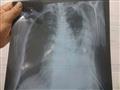

أجرى الأطباء في مستشفى دسوق العام، بكفر الشيخ، أول عملية من نوعها لشق صدر مريض مسن، في ظل الإمكانيات المحدودة، التي تعاني منها أغلب المستشفيات الحكومية.

وقاد الدكتور وسيم عطية، أستاذ مساعد جراحة القلب والصدر، بطب جامعة الأزهر، فريقًا طبيًا، ضم الدكتور أحمد عليبة استشاري التخدير، وعددًا من طاقم التمريض، والعاملين، لإجراء الجراحة، لرجل عجوز يبلغ من العمر 72 عامًا، يقيم بإحدى القرى التابعة لمركز دسوق، تعرض لحادث سير، أسفر عن إصابته بكسور متعددة، في الضلوع ونزيف بالصدر، وتهتك بالرئة.

وبدأ الفريق الطبي، مهام عمله بتركيب قسطرة، تصريف صدر، لتفريغ النزيف، وجرى حجز الحالة بالعناية المركزة، وعمل الفحوصات الطبية اللازمة، حتى تقرر له إجراء الجراحة، والتي استغرقت حوالي 5 ساعات متواصلة، عبارة عن شق الصدر بالكامل، وإصلاح بعض الضلوع فيه، وكذا إصلاح جدار الصدر، وتقشير القشار البلوري، وأيضًا إصلاح تهتك الرئة.